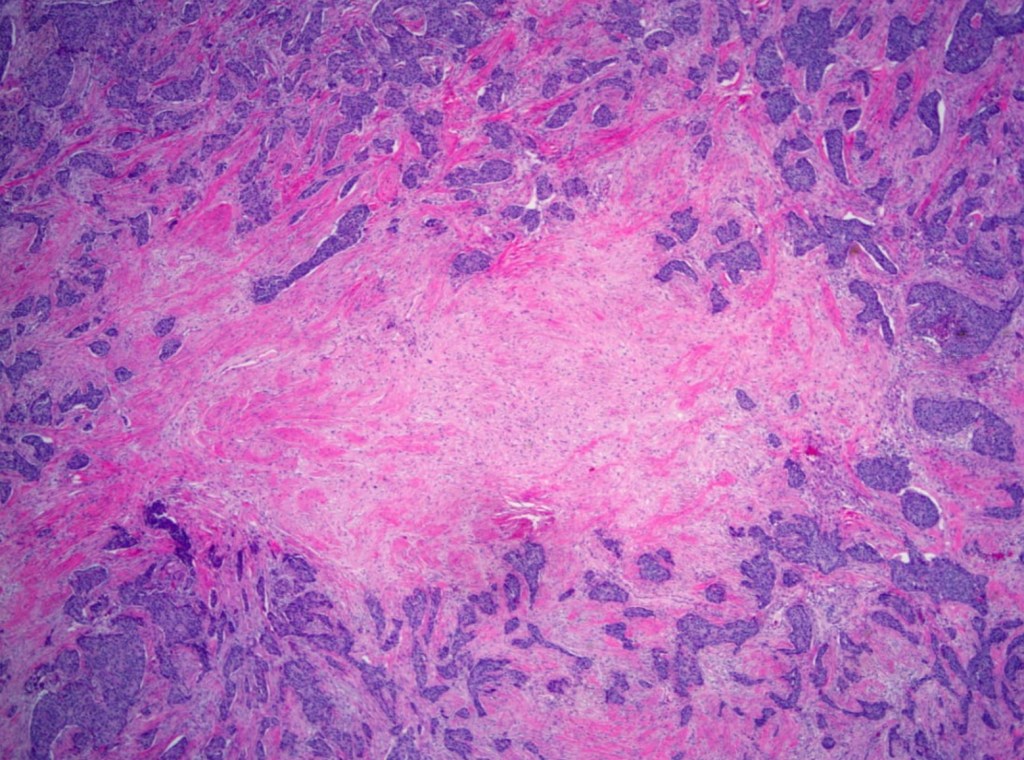

- The majority of TNBCs are of:

- Invasive ductal breast cancer, no special type:

- Characterized by:

- High mitotic indices

- Presence of central necrotic or fibrotic zones

- Pushing borders

- Conspicuous lymphatic infiltrate

- Typical or atypical medullary features